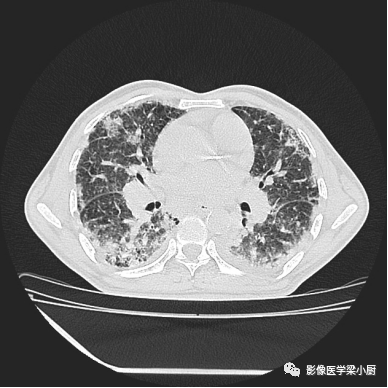

1.分布:90%的IPF患者HRCT表现为胸膜下分布。

分布的不均匀性:HRCT肺外周部位和胸膜下区不均匀分布,正常肺组织和病变区(网格、牵拉性支气管扩张或蜂窝)交替。病变常呈双侧不对称分布。

2.网格:网格影一般分布于两肺基底部、胸膜下,常伴结构扭曲。网格影不等同于小叶间隔增厚。

3.蜂窝:呈镞状囊性低密度影,囊壁光整,厚度1~3mm,直径常为3~10mm,偶尔可达2.5cm。蜂窝是HRCT的UIP型最具特征性的表现,蜂窝影预测UIP的灵敏度和特异度较高。

蜂窝的组成目前尚不清楚,推测为扩张的小气道,是纤维化进展的标志,提示预后差。

双肺呈弥漫蜂窝状改变

4.磨玻璃密度影:网格内磨玻璃密度影(ground-glass opacification,GGO)代表低于HRCT分辨率的肺纤维化病变,一般不超过网格范围。

而网格、蜂窝及牵拉性支气管扩张、细支气管扩张范围外的GGO则提示感染或其他疾病。

5.肺结构扭曲:影像学上将肺结构扭曲定义为肺小叶结构的改变(从多边形到变小的三角形)、非节段分布(跨越叶间裂胸膜);还可表现为胸膜表面和支气管血管束不规则。

6.尖-基底分布:UIP典型分布于基底部,但也可分布于上肺。当肺基底部以上肺区内出现网格影,同时伴肺下叶蜂窝影,可诊断UIP。